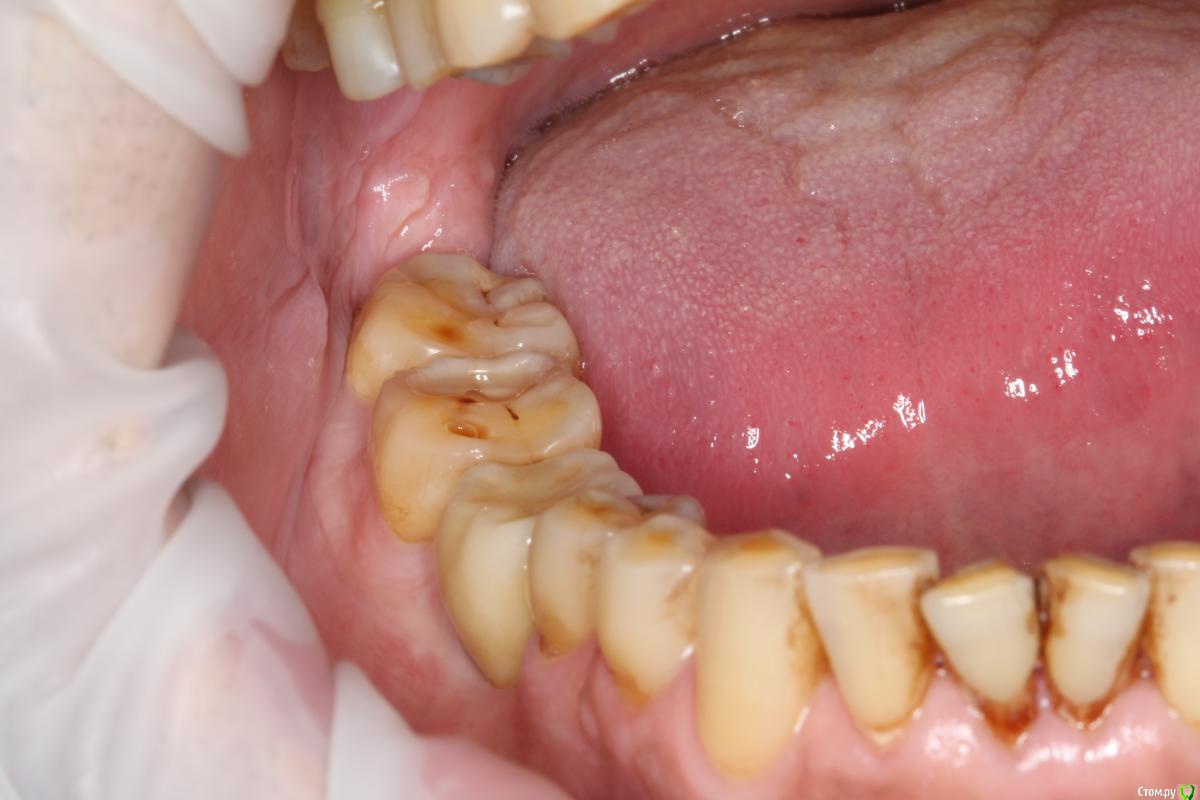

Robinbobin Опубликовано 27 марта, 2015 Поделиться Опубликовано 27 марта, 2015 (изменено) Пациент 57 лет с жалобами на стираемость зубов,чувствительность и бруксизм Хотелось бы услышать ваше мнение!!!! Изменено 27 марта, 2015 пользователем Robinbobin Ссылка на комментарий

Robinbobin Опубликовано 28 марта, 2015 Автор Поделиться Опубликовано 28 марта, 2015 а с чем к вам этот пациент пришел с какой проблемой?С жалобами на стираемость,чувствительность зубов!!! Ссылка на комментарий